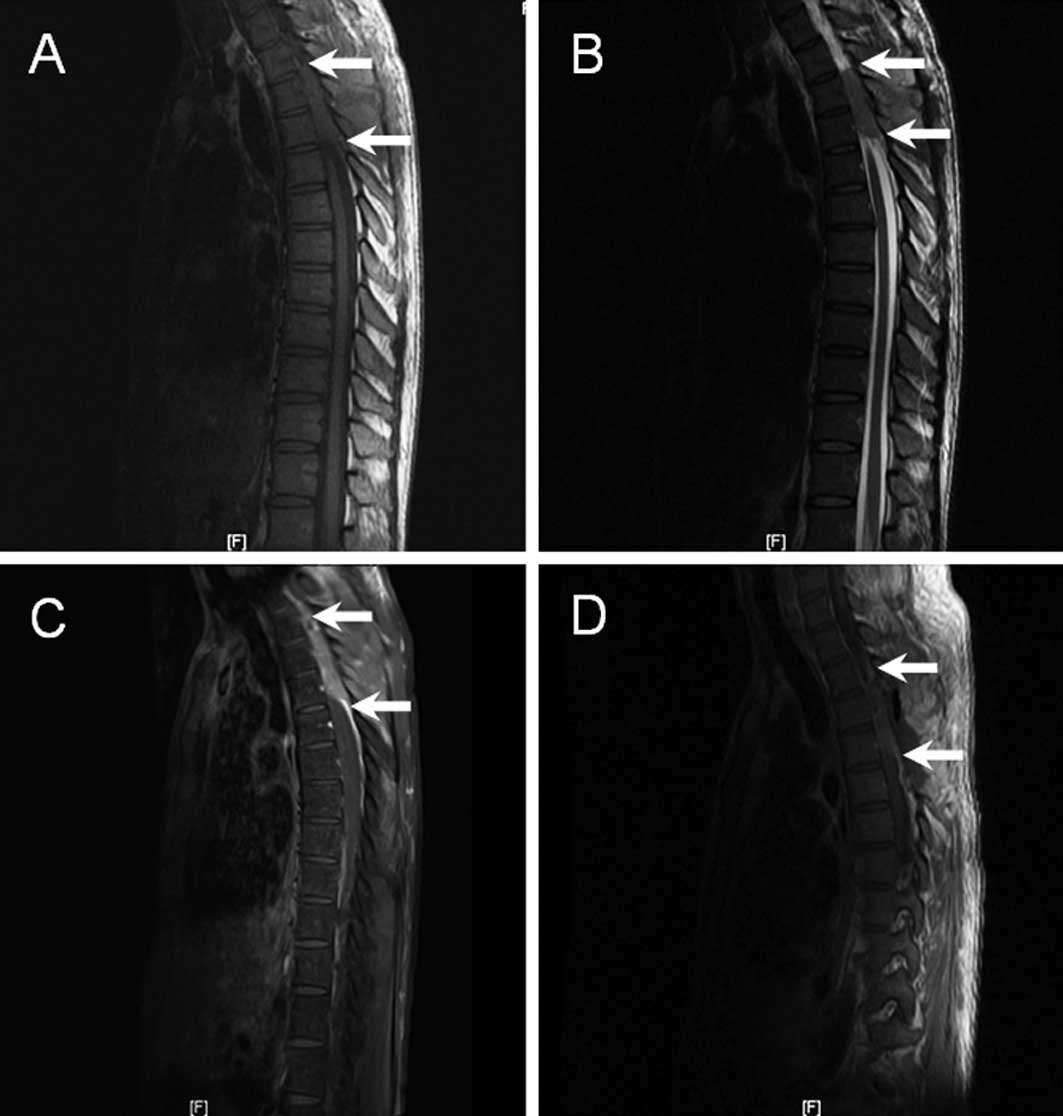

This report presents the case of a 35-year-old male with no significant clinical background. At the time of referral to The First Affiliated Hospital of Fujian Medical University (China), the patient had suffered from thoracic back pain for 2 months and progressively ascending bilateral numbness and weakness of the lower extremities for 1 month. Shortly following a visit to the neurology clinic, the patient became unable to walk independently and developed urinary incontinence. Neurological examination revealed that muscular strength was normal in the upper limbs, but decreased in the lower limbs (grade 1/5 strength in the left and grade 2/5 in the right). Muscular tension increased in the lower limbs. Superficial and deep sensation disturbance was found below the level of T5 for the left side and T6 for the right side, respectively. The reflexes did not exist in the two sides, including cremaster, patellar tendon and abdominal wall at the upper, middle and lower level. Signs of Babinski, Oppenheim, Chaddock and Gordon were positive in the two sides. Cranial computed tomography (CT) and magnetic resonance imaging (MRI) were normal. Plain MRI of the thoracic spine revealed an epidural mass (6.4×1.4×4.2 cm), which was located at the T2–T4 level where it compressed the spinal cord. The mass was isointense to the spinal cord on the T1-weighted image (Fig. 1A) and hyperintense on the T2-weighted image (Fig. 1B), with a moderate and homogenous contrast enhancement (Fig. 1C). Bone destruction was observed in the corresponding spinal and vertebral plate. The right lateral neighboring muscles were not well organized.

Figure 1

Sagittal MRI of the thoracic spine revealed an epidural mass at the level of T2–T4 where it compressed the spinal cord (arrowheads). (A) T1-weighted image at the onset of disease demonstrating isointensity to the spinal cord; (B) T2-weighted image at the onset of disease demonstrating hyperintensity to the spinal cord; (C) enhanced T1-weighted image at the onset of disease demonstrating a moderate and homogenous contrast enhancement; (D) enhanced T1-weighted image following vertebral canal decompression demonstrating the remaining mass still existed in the same position and compressed the spinal cord. MRI, magnetic resonance imaging.